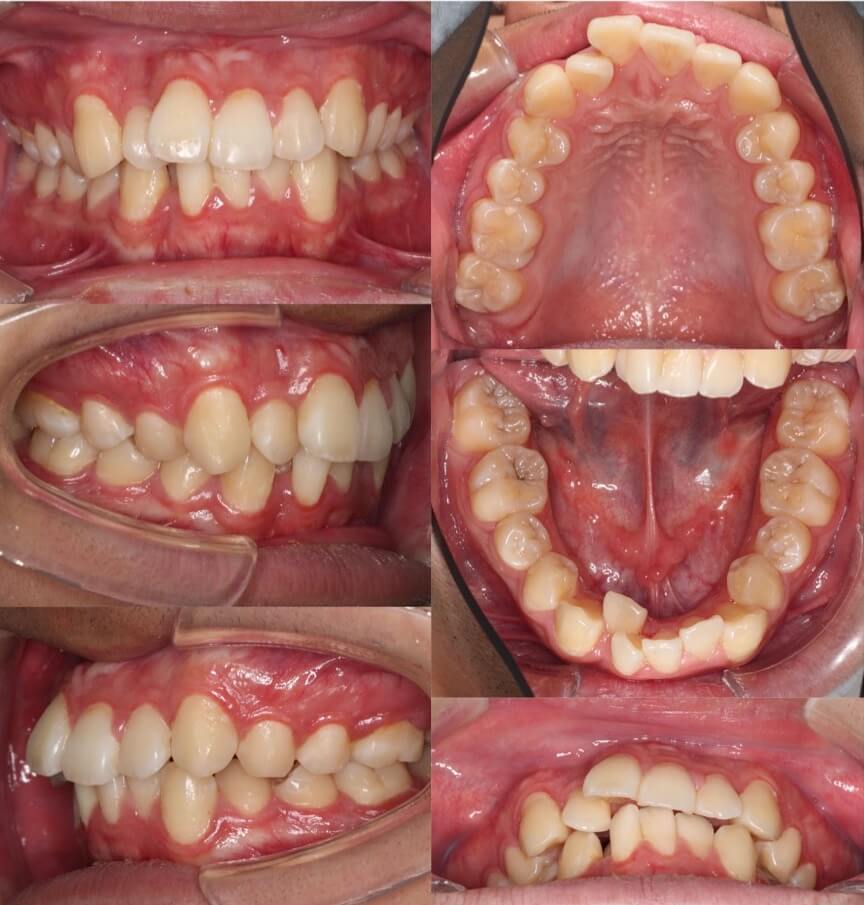

「男性は顔が引き締まる」

高校生男性・唇側矯正装置・下あご後退型

当初は、抜歯矯正治療にするかしないかで、治療方針に迷ったケースですが、最終的には患者さんの希望に沿って抜歯矯正治療にしました。歯の動きがゆっくりであったため、治療期間が3年を超えてしまいました。

<症例概要> 難易度:★★★★☆

主訴:口元の突出・前歯のガタツキ

年齢・性別:高校生男性

住まい:千葉県八千代市市

症状:下顎後退・叢生

治療方針:抜歯空隙の閉鎖(最大固定)

治療装置:唇側矯正装置

固定:歯科矯正用アンカースクリュー(頬側x2)

抜歯:上下第一小臼歯(計4本)

治療期間:3年4か月

リテーナー:上下プレートタイプ+フィックスタイプ

治療費用:968,000(税込)

代表的副作用:痛み・治療後の後戻り・歯根吸収・歯髄壊死・歯肉退縮